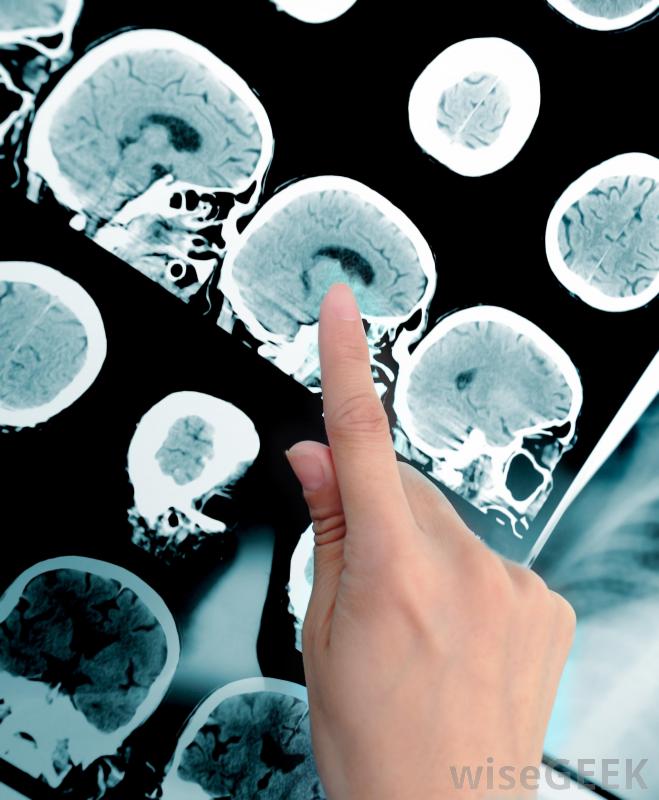

醫療專業人員使用核磁共振儀診斷內部疾病。

核磁共振技術人員經常從相鄰房間觀察手術過程。